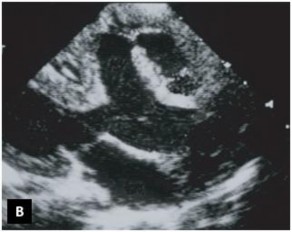

Tiếp theo đó, mặt cắt cạnh ức cao trên trục ngắn cho phép đánh giá tương quan giữa hai đại động mạch và mối liên quan của chúng với lỗ TLT, đánh giá tình trạng của đường ra của các tâm thất (Hình 1.13). Mặt cắt này còn giúp đánh giá xuất phát và đường đi của hai ĐMV. Mặt cắt cạnh ức thấp trên trục ngắn cho phép khảo sát tình trạng của thân và hai nhánh của ĐMP [59],[83].

Hình 1.13: Mặt cắt cạnh ức trong chẩn đoán TPHĐR. (A) Hình ảnh TPHĐR thể chuyển gốc qua mặt cắt cạnh ức trục dài. (B) Mặt cắt cạnh ức trục ngắn cho hình ảnh TPHĐR thể chuyển gốc với ĐMP cưỡi ngựa lên VLT 50% [53]